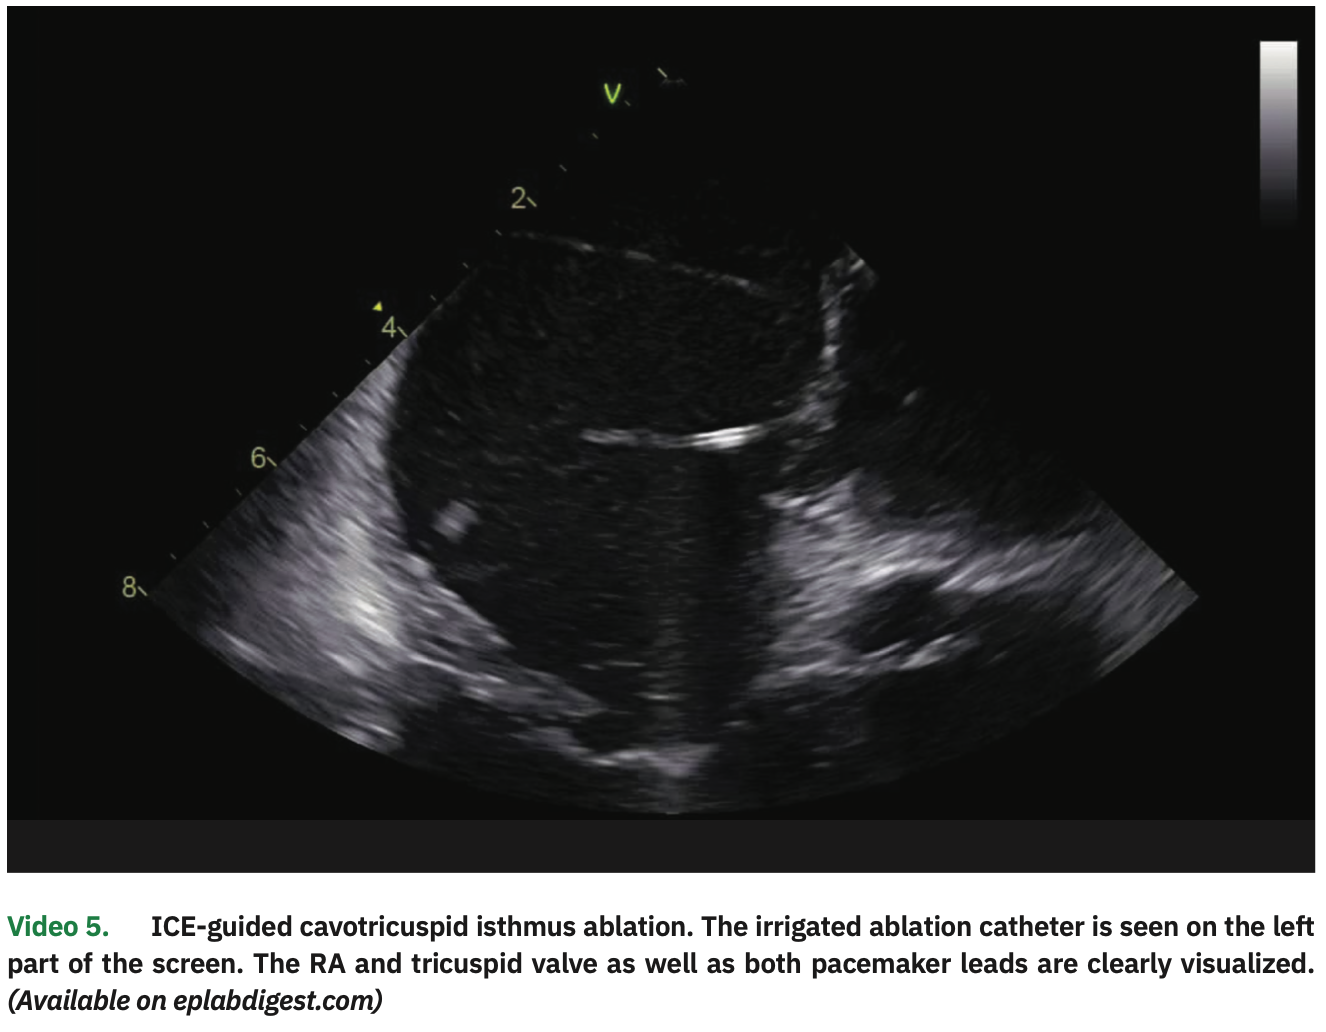

Atrial pacing with 3 extrastimuli (320/320/320 ms) easily induced typical atrial flutter. The ablation catheter was then pulled to the RA, and a linear lesion in the cavotricuspid isthmus (CTI) resulted in interruption (Video 5). Detailed ICE visualization was important to avoid tangling the catheter with the pacemaker leads and to guide tissue contact all along the CTI.